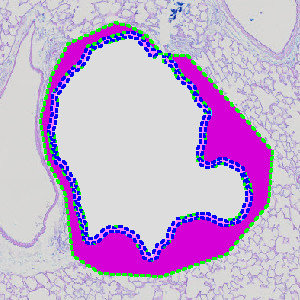

Figure 5

Results of analysis with the APP: “02 Mucous Detect”. The bright blue label identifies the basal lamina, and the dark blue label identifies the intraepithelial mucosubstances. The bright pink label denotes the epithelial tissue, and the dark pink denotes the remaining tissue.

Methods

The first image processing step takes place inside the manually outlined general region of interest (ROI), and involves the segmentation of the tissue into epithelial tissue and remaining tissue as shown in figure 3. Secondly, the basal lamina is identified as the border between the epithelial tissue and the remaining tissue (see FIGURE 5). Afterwards the intraepithelial mucosubstances are identified based on a linear Bayesian classification combined with prior knowledge of the size of mucusubstances (see FIGURE 5.) Finally, relevant output parameters, such as the basal lamina length and the mucous area, are quantified.